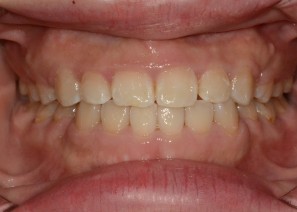

Before & After

- 돌출입교정

Before

After